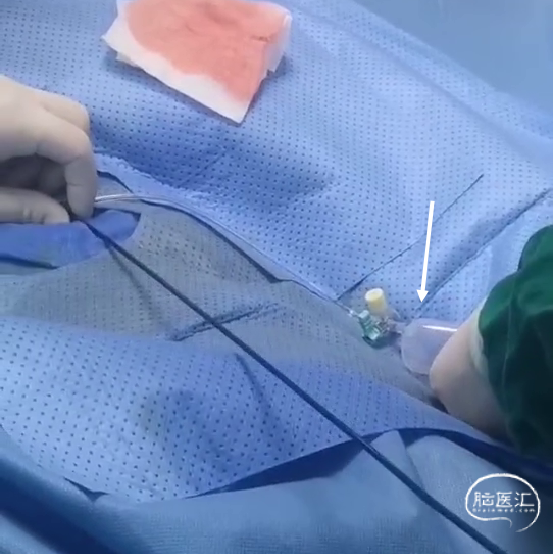

不减影图像中长鞘(白色箭头)和抽吸导管(红色箭头)位

持续接触抽吸90秒后,回撤抽吸导管;抽吸导管进入长鞘之前,开启长鞘负压抽吸;发现血栓卡在长鞘头端、抽吸导管撤出长鞘后发现长鞘内无回血(白色短箭头)。20ml注射器连接长鞘、持续负压抽吸下撤出长鞘;长鞘在进入8F穿刺鞘前,开启穿刺鞘负压抽吸(白色长箭头)。最终成功将血栓从长鞘内抽吸出。